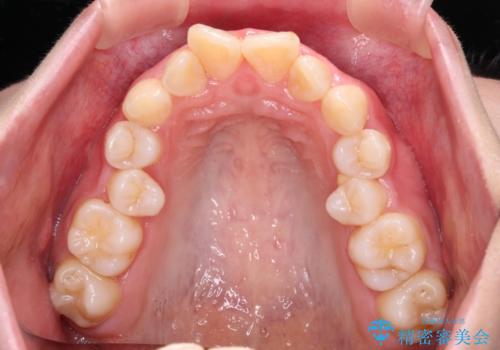

極端な出っ歯という訳ではありませんでしたが、叢生が強かったため、上下左右の第一小臼歯4本を抜歯し、少しでも口元の突出感を改善できるよう治療計画を立案しました。

下顎前歯が隠れるほどのディープバイトであり、それによる顎の負担も大きかったため、ディープバイトもしっかりと改善できるよう、表側のワイヤー装置にて矯正治療を行うこととしました。

ディープバイトは、治療を行っていた我々も驚くほど、短期間で劇的に改善することができました。

骨格的に下顎骨が左側にシフトしていたため、上下正中の位置や左側臼歯部の咬合を理想的に仕上げることはできませんでしたが、非常に綺麗な口元を達成することができました。